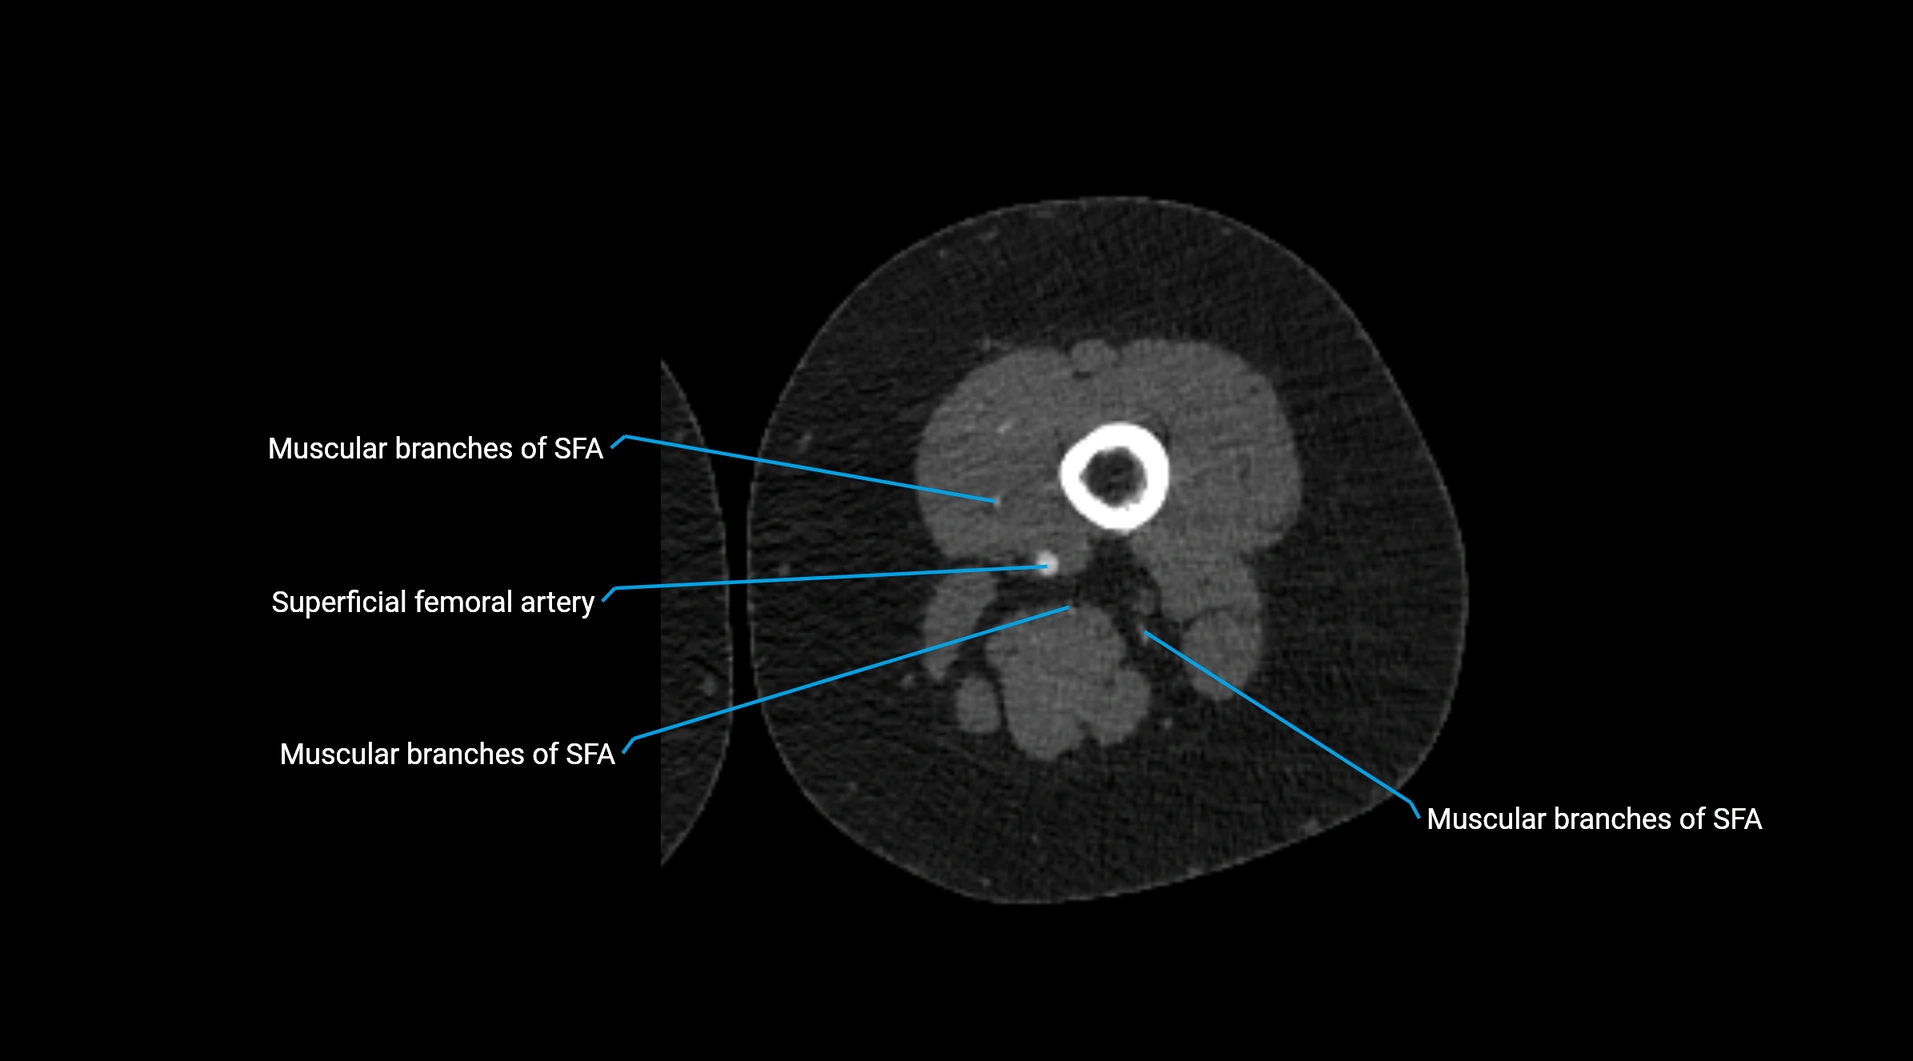

CT images

image

CT Appearance

Non-contrast CT:

• Appears as a tubular soft tissue structure anterior to vertebral bodies

• Calcified atherosclerotic plaques appear as hyperdense foci along the wall

• Useful for screening abdominal aortic aneurysm (AAA) size and mural calcification

Contrast-enhanced CT (CTA):

• Gold standard for abdominal aortic imaging

• Provides excellent detail of lumen, wall, aneurysm, thrombus, and branch vessels

• Multiplanar and 3D reconstructions help in aneurysm measurement, stent graft planning, and dissection evaluation

• Detects acute rupture, traumatic injury, or occlusion with high sensitivity